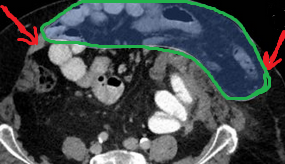

Very large incisional hernia. Red arrows - Separated abdominal walls - atrophic rectus abdominis muscle (Courtesy Dr. V. Penopoulos)